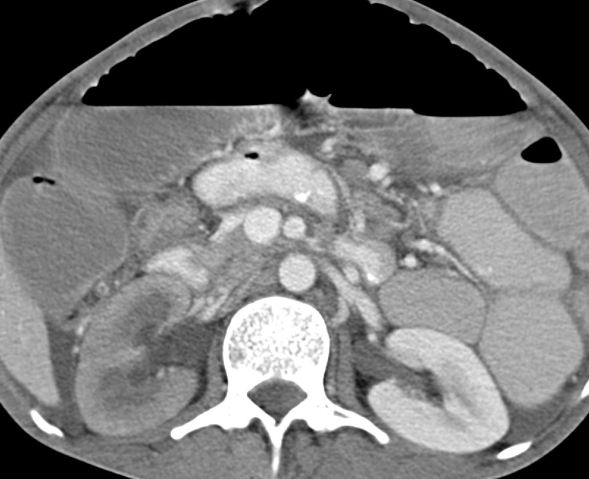

For example, look here at the detailed description of the post-op findings by my sincere resident. I would instead just state ‘The patient is status post Whipple’s procedure, with expected post-operative findings. The post-operative drain is in appropriate position. Small 5 cc collections present in the foramen of Winslow and near the pancreatico-jejunostomy site. Mild perihepatic and perisplenic fluid, within expected limits. No other collection.’